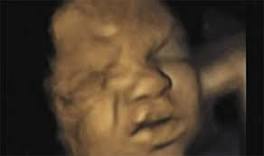

Alabama is the latest state where a pro-life piece of legislation to ban dismemberment abortions is advancing and yesterday the legislature approved ...